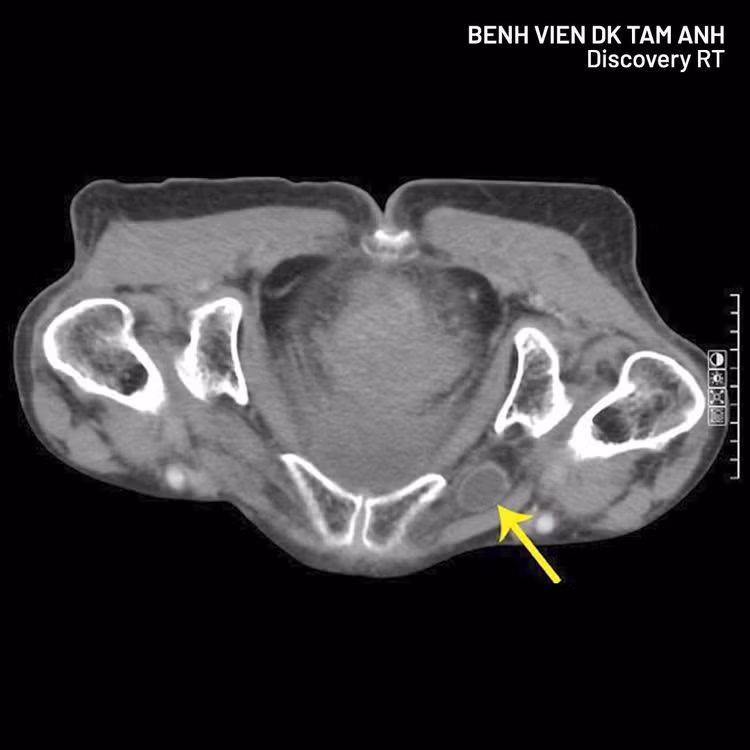

Hình ảnh thoát vị qua CT - Ảnh BVCC

Qua hình chụp CT, phát hiện quai ruột non chui qua lỗ bịt gây tắc ruột. Nếu chậm trễ, nguy cơ hoại tử ruột, thủng ruột và đe dọa tính mạng rất cao. Nhờ thăm khám kỹ lưỡng kết hợp chẩn đoán hình ảnh hiện đại, nguyên nhân nguy hiểm đã được phát hiện kịp thời, giúp người bệnh tránh biến chứng nặng.

Trước tình trạng của bà Thoa, ê-kíp nhanh chóng lựa chọn phẫu thuật nội soi cấp cứu. Hình ảnh CT cho thấy quai ruột chưa hoại tử, tạo điều kiện can thiệp kịp thời, tránh phải mổ mở và cắt ruột nhiều rủi ro.